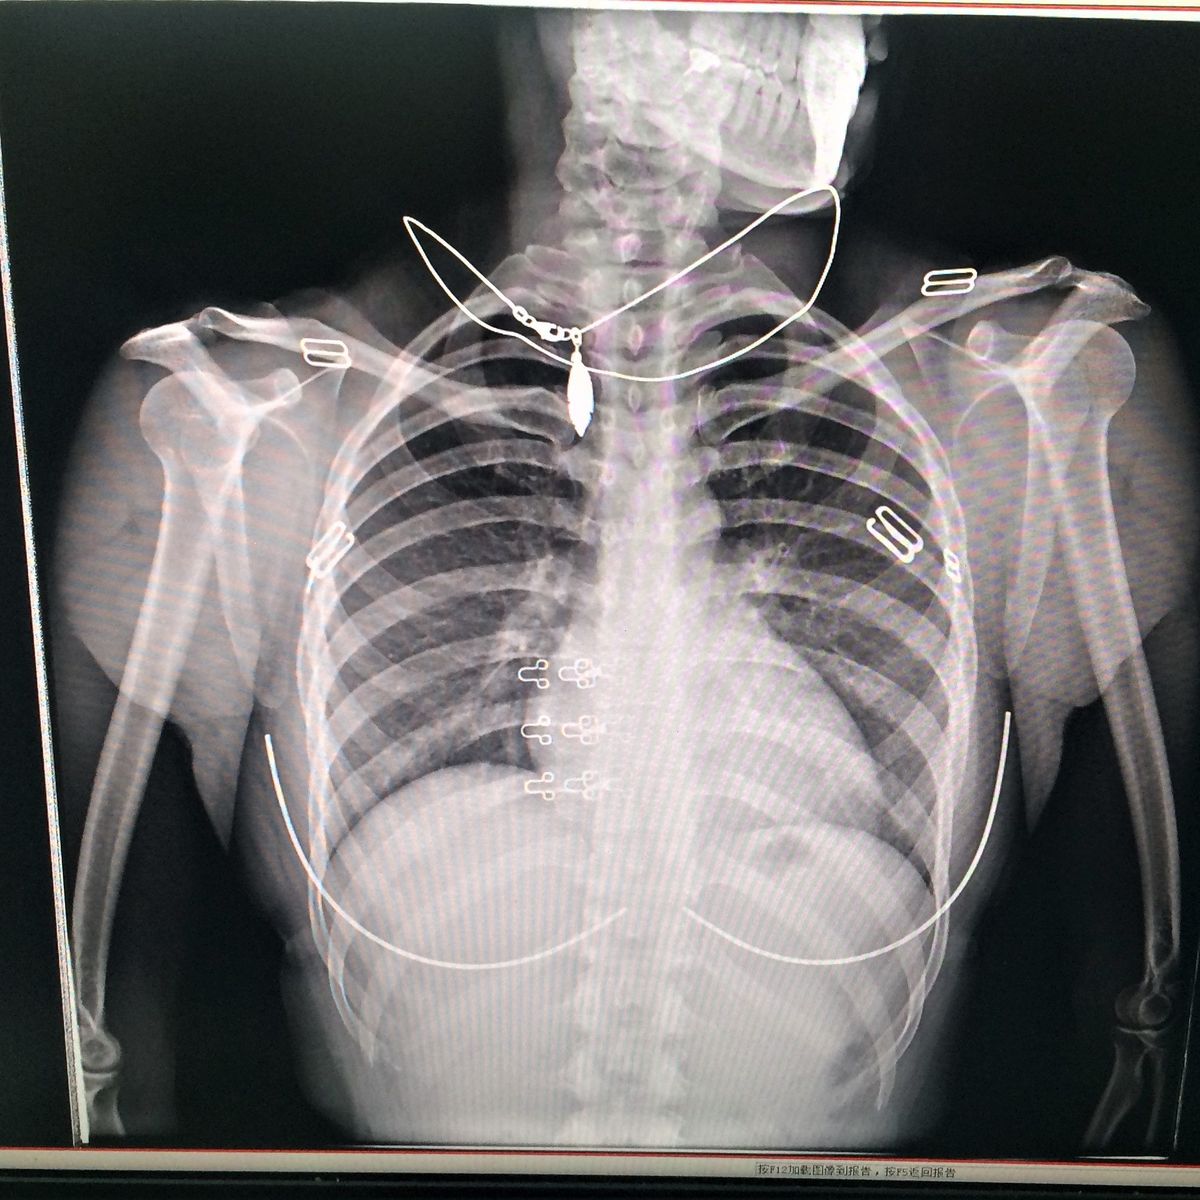

For this type of pneumonia performing a chest x-ray on the. Chest x-rays can reveal areas of opacity seen as white which represent consolidation. In complicated cases of pneumonia perform chest radiography 6 weeks after treatment to verify resolution of the pneumonia and to screen for any underlying predisposing.

Baby chest x ray pneumonia Thursday March 24 2022 Respiratory syncytial virus or RSV most commonly seen in children under age 5 Parainfluenza virus. Pneumonia is not always seen on x-rays either because the disease is only in its initial stages or because it involves a part of the lung not easily seen by x-ray. An important test for making a diagnosis of pneumonia is a chest x-ray.

Doctors typically rely on a physical exam and tests. Pulmonary consolidation is a non-specific term for pulmonary opacities seen on radiography that are the result from a process that fills the alveolar spaces further discussion here. Baby chest x ray pneumonia.

This chest X-ray shows an area of lung inflammation indicating the presence of pneumonia. However chest X-ray examinations for pneumonia detection are prone to subjective variability 2 3. Please see disclaimer on my website.

It determines the pathogen that could have caused pneumonia. The differential for the radiologic finding of pulmonary consolidation includes blood pulmonary hemorrhage pus infection ie. We investigate whether chest radiographic findings could be used as predictors of severity of childhood pneumonia.